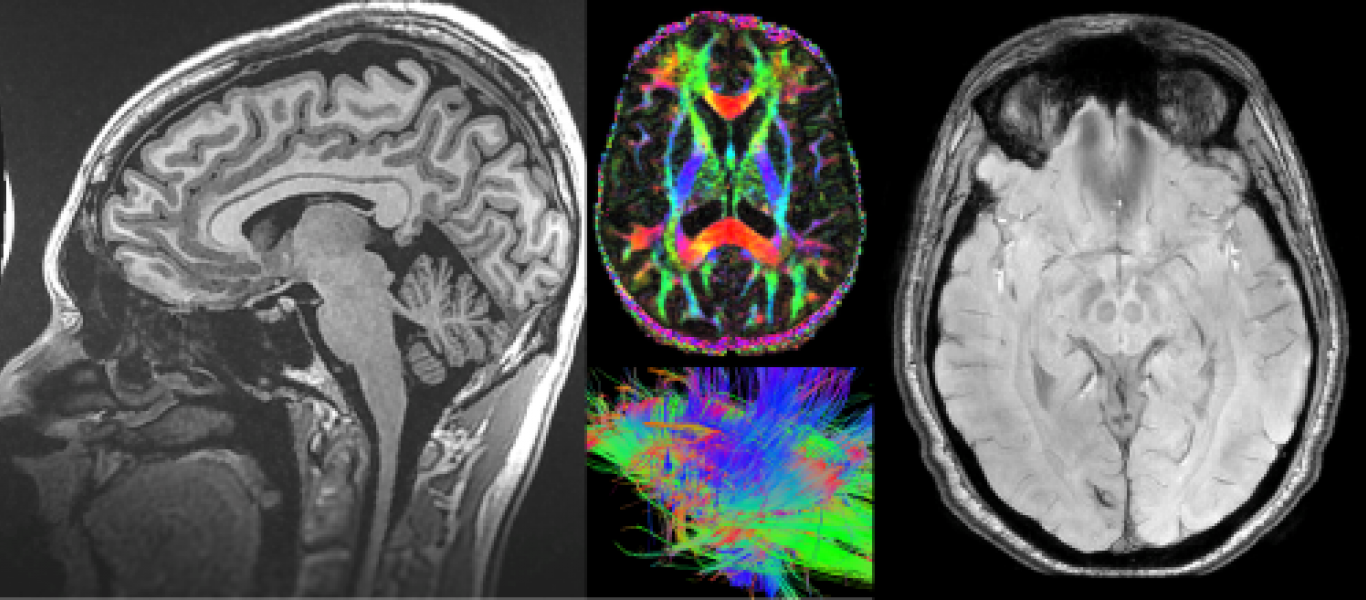

To introduce fundamental principles of the physics of conventional radiologic imaging techniques, digital radiography, and advanced imaging modalities.